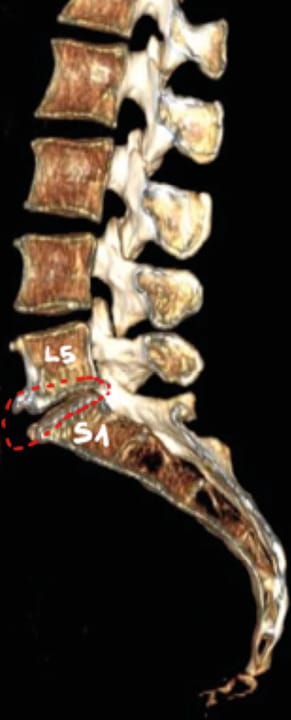

Neurologie Neurostimulations manuelles et lombosciatique : apport de la Posturothérapie NeuroSensorielle (PNS)